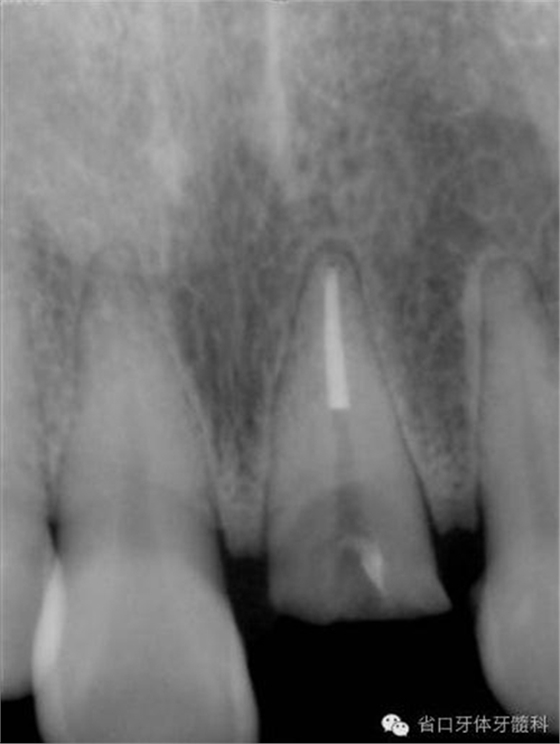

圖8. 21/行根管治療術(shù),保留根尖約5mm的根充物,根中上段預(yù)留空間以預(yù)備纖維樁道。